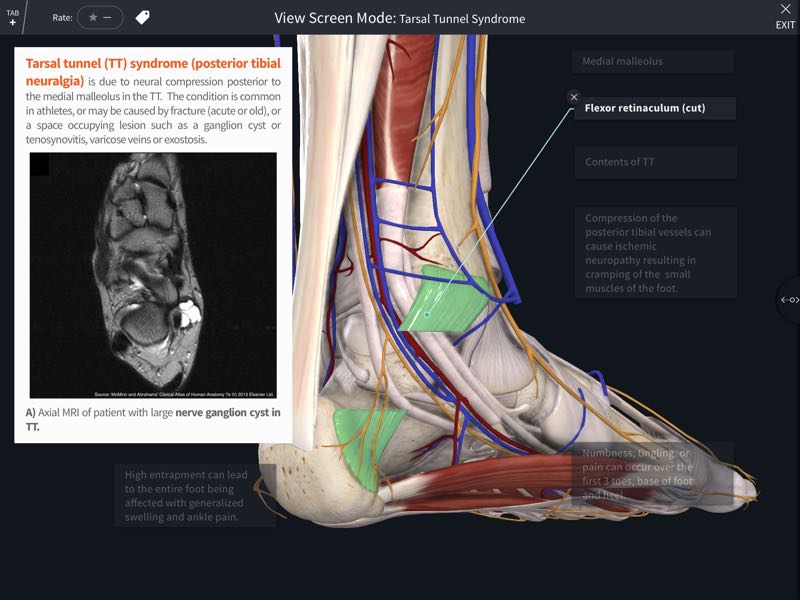

Point of Care Ultrasound